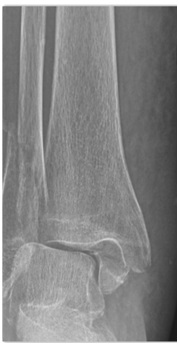

Con fecha 03/04/2017, tras haber sufrido caída casual, acude al servicio de urgencias del hospital de referencia, donde se diagnostica fractura-luxación bimaleolar de tobillo derecho (Fig. 1) y se decide ingreso hospitalario.

Fig. 1. Rx de fractura tras caída casual